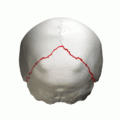

Skull seen from behind. Showing λ-like shape of the lambdoid suture.

Lambdoid suture with wormian bones, seen from behind.